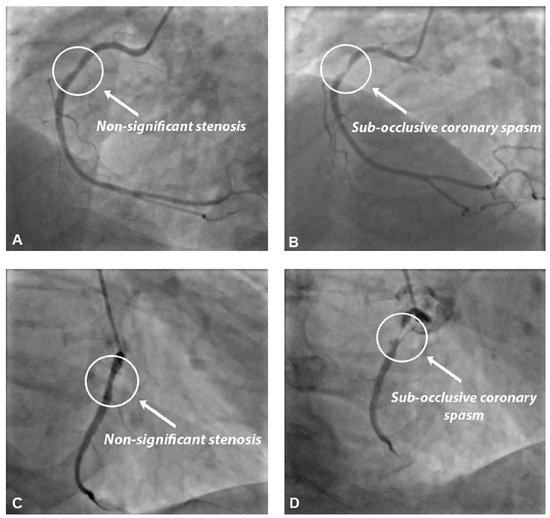

A routine 1-year follow-up exercise stress test was performed while the patient was asymptomatic and without interruption of β-blocker therapy. His treatment at the moment of the exercise stress test included aspirin (100 mg 1×/day), lisinopril (20 mg 1×/day), pravastatin (40 mg 1×/day) and atenolol (25 mg 1×/day). During the exercise stress test the patient was pain free. However, as shown in Figure 1, significant ST-segment elevation occurred in all inferior leads. This ST-segment elevation appeared during the effort phase and persisted throughout the recovery phase. The patient was then referred for coronary angiography, which showed a non-significant stenosis (less than 50% of the reference vessel diameter) in the proximal-mid portion of the right coronary artery. During diagnostic coronary angiography, a 1000 µg intracoronary nitroglycerin bolus was administered in order to better assess reference vessel diameter and stenosis severity. A few seconds after intracoronary nitroglycerin injection, asymptomatic paradoxical subocclusive coronary spasm, superimposed on the previously described plaque, was observed (Figure 2), suggesting a diagnosis of vasospastic angina for this patient. Of note, no drop-in of the catheter tip, which is quite common during right coronary artery cannulation and frequently associated with coronary spasm, was observed during coronary angiography. No deep intubation of the right coronary artery occurred. Because of the transmural ischaemia documented on the exercise stress test, a drug-eluting stent was implanted in the right coronary artery. Interestingly, the spasm was sustained and lasted until stent implantation. The clinical evolution was favourable and a 1-month follow-up exercise stress test was clinically and electrically negative. Holter monitoring did not show any transient ST-segment elevation and the patient did not experience any episodes of chest pain during 6 months of follow-up.

Figure 2. Panel A: Basal coronary angiography, showing a non-significant (less than 50% of the reference vessel diameter) stenosis in the proximal-mid portion of the right coronary artery. Panel B: Following intracoronary nitroglycerin injection, sub-occlusive coronary spasm, superimposed on the previously described coronary plaque, was observed. Panel C and D: Basal angiography and focal coronary spasm observed in another projection.